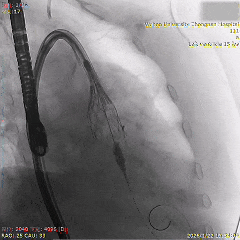

全展开位评估:左右重合体位造影可见无冠窦侧深度约为瓣下3mm

全展开位评估:左冠切线位造影可见左窦侧深度约为瓣下5mm